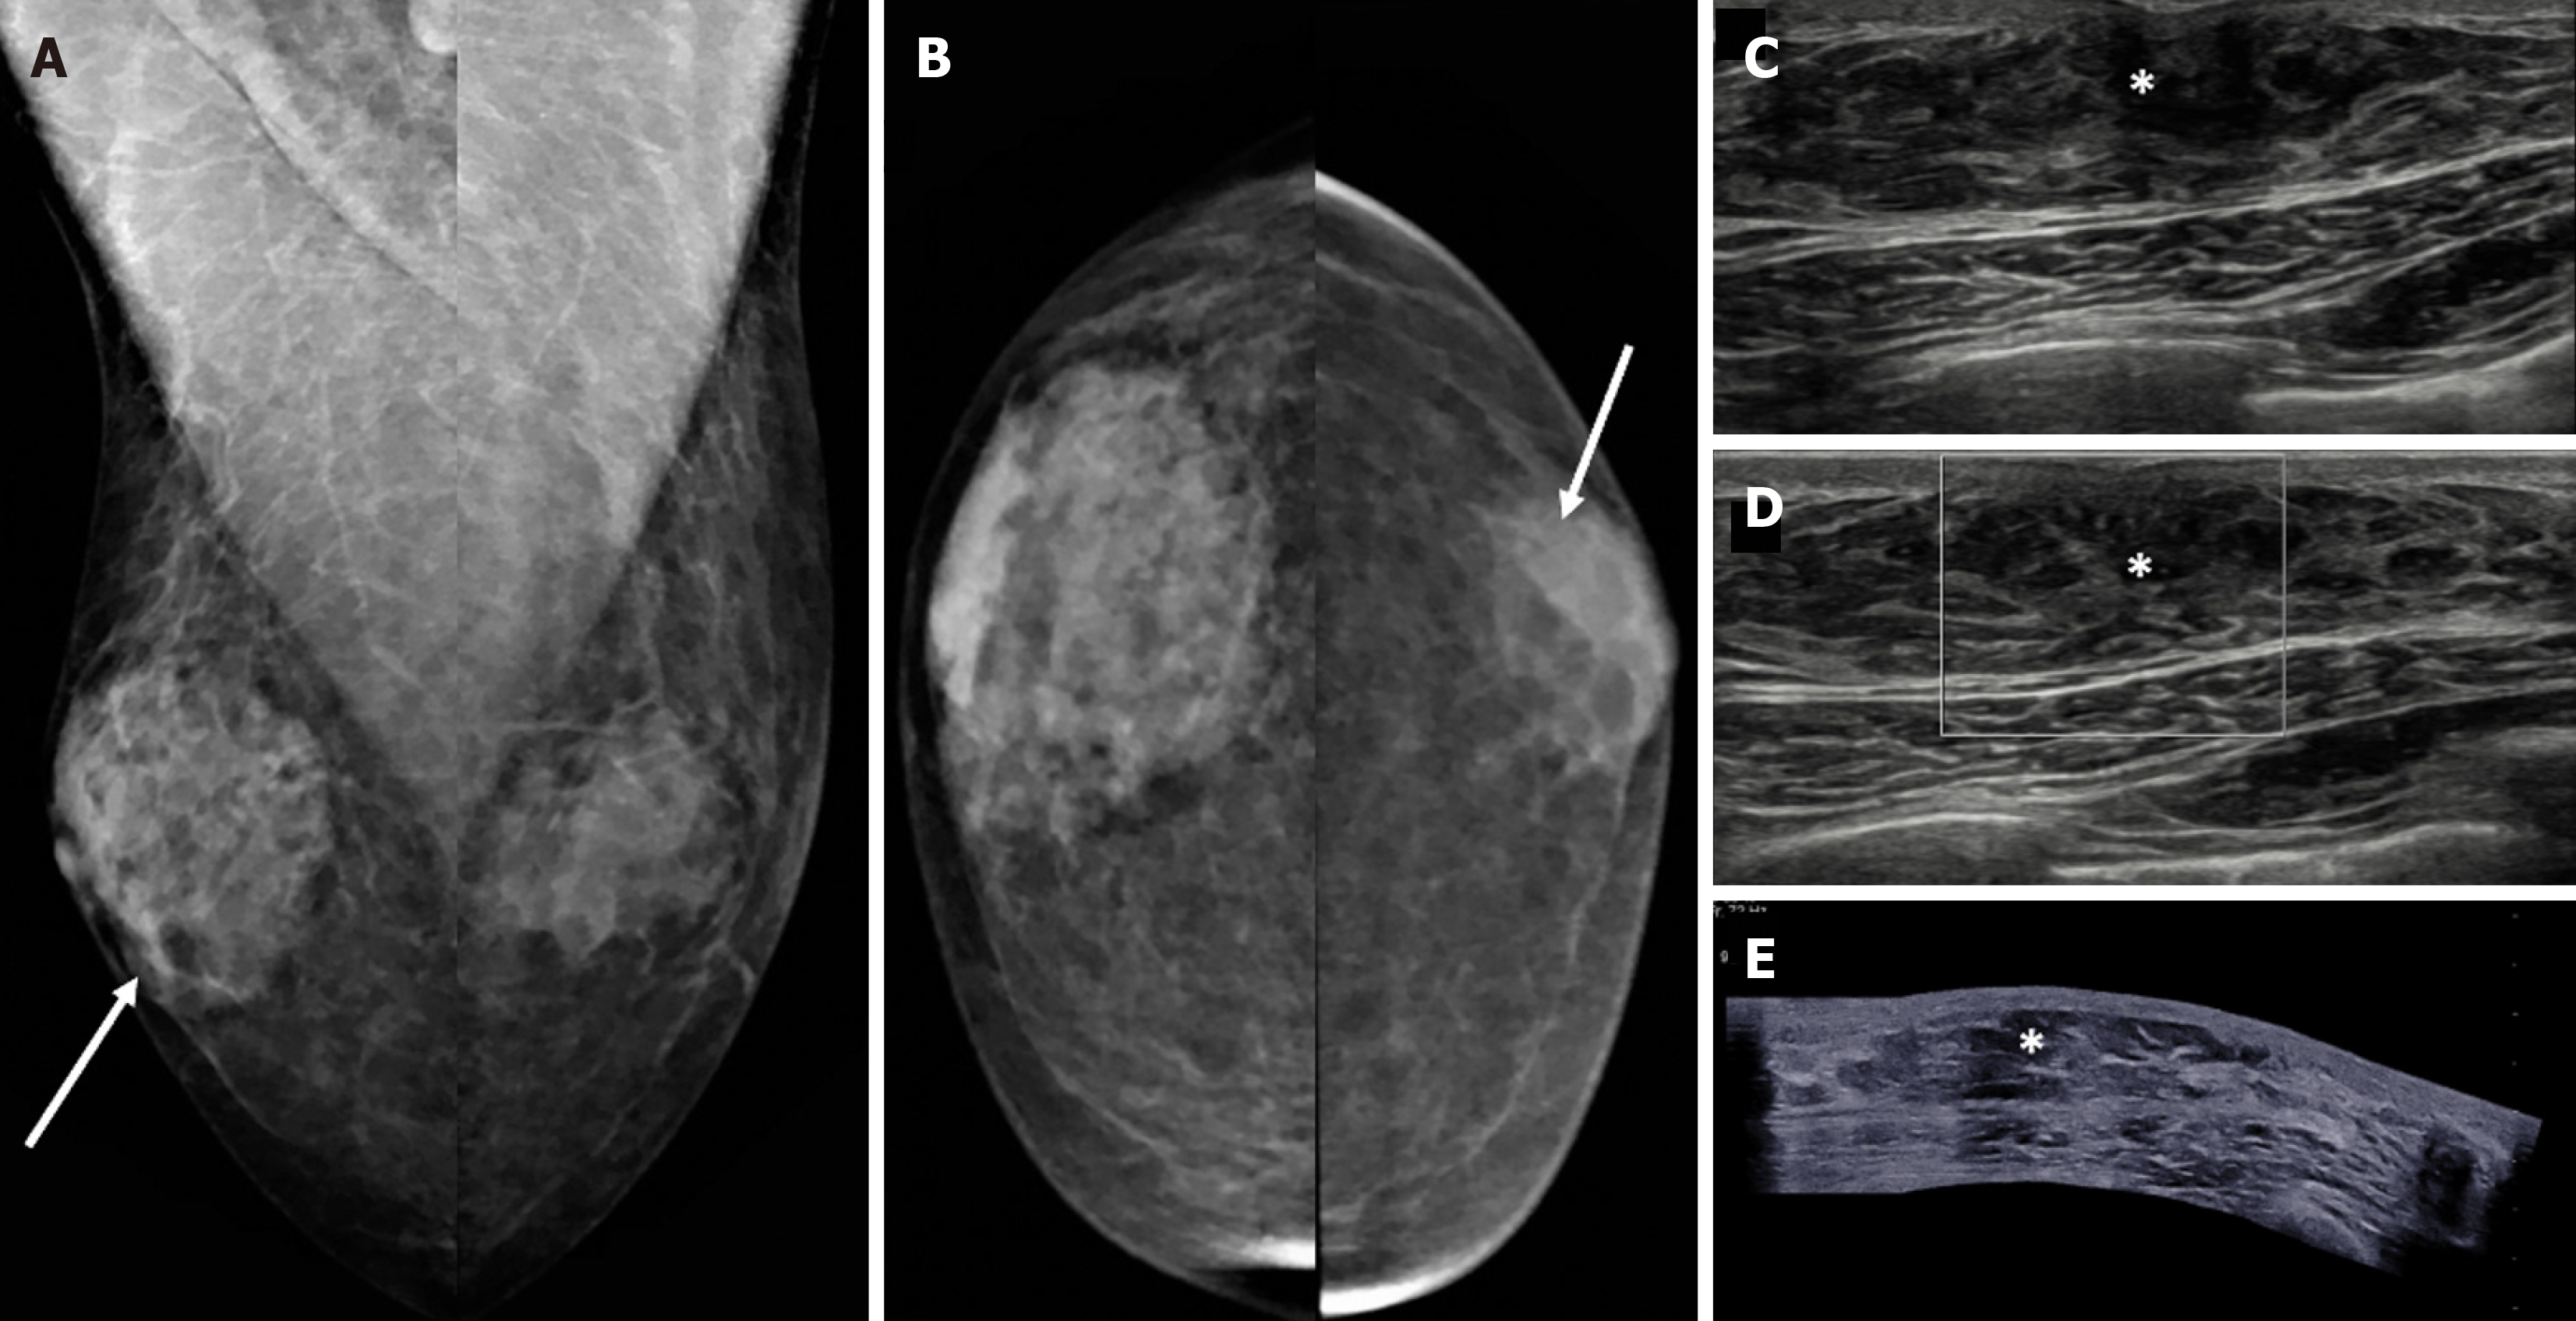

Figure 4 Nodular gynecomastia in a 62-year-old male with tender subareolar masses in bilateral breasts.

A: Mediolateral oblique; B: Craniocaudal mammography views show oval equal density masses in the retroareolar locations of both breasts (white arrows); C-E: Ultrasound images [C, D (color Doppler) and E (panoramic views)] demonstrate an oval parallel indistinct hypoechoic area (denoted by asterisks) in the retroareolar location with no evident vascularity, which is consistent with gynecomastia.